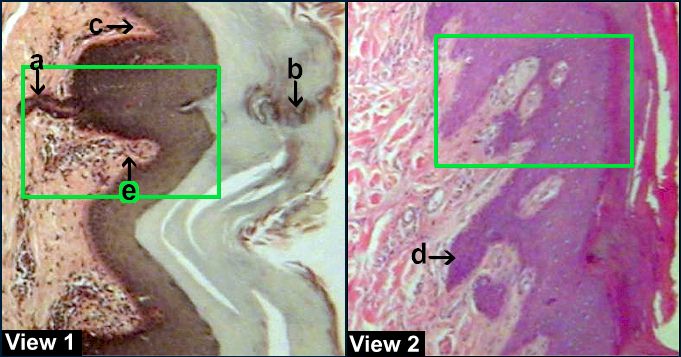

Thick Skin and Meissner's Corpuscle - 40X

a Part of a sweat gland b Sweat gland duct

c Dermal papillae d Dermal peg

e Meissner's corpuscle. Click on green square to see details.